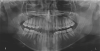

Fig 7. Panoramic x-ray of patient.

Figure 7